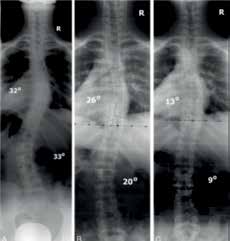

Die konservative Behandlung der Skoliose mittels einer Orthese hat dank der aussagekräftigen Studie zur Effektivität der Orthesenversorgung von Weinstein et al. ein verstärktes weltweites Interesse gefunden 16. In einer Vorstudie zur Effektivität der TLI-Orthese wurden bei 40 Kindern mit einer zweibogigen Skoliose Röntgenaufnahmen in stehender Position ohne Korrektur und in liegender Position ohne und mit einer im thorakolumbalen Übergang untergelegten, wie ein Widerlager wirkenden Rolle angefertigt (Abb. 5a–c). Der Vergleich der Aufnahmen zeigte mit thorakolumbaler Pelotte eine statistisch signifikante (p < 0,001) Korrektur des Cobb-Winkels beider Krümmungen 17 (Abb. 6a–c).